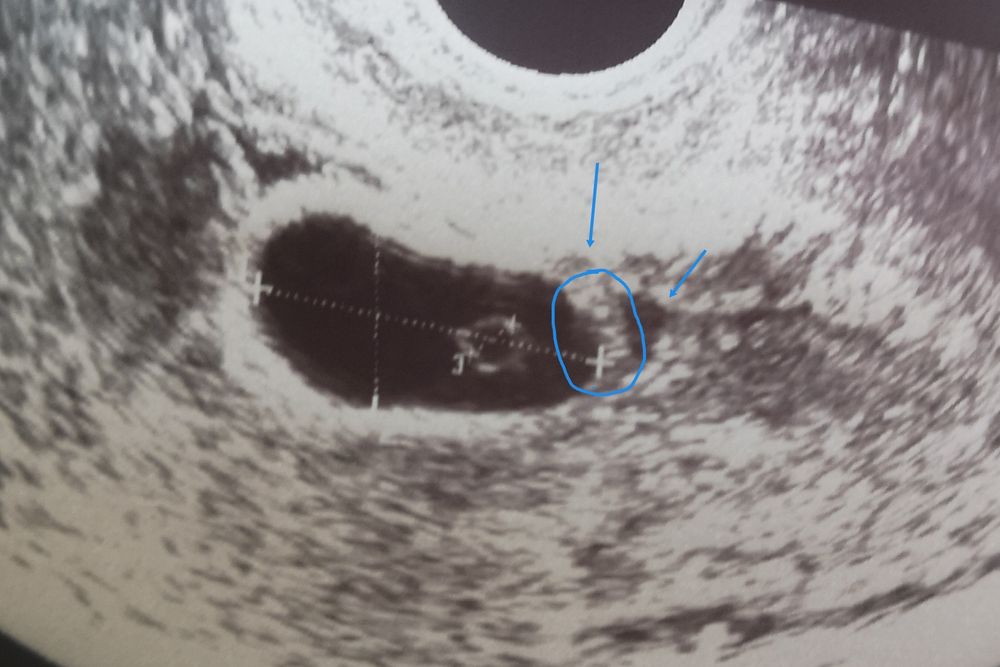

У вас хорошая динамика, но скорее всего неправильно рассчитан срок. Может яйцеклетка позже вышла, может дольше по трубам гуляла, может прикрепление позднее, не знаю. Но главное, повторю, динамика. Для вашего размера ПЯ, нормально что не видно эмбрион. У меня при ПЯ 20 мм кое-как разглядели, и то, только второй врач, под каким-то другим ракурсом нашла, минут 5 искали. То, что вы указали это не Э, его не перепутаешь, Тк должна быть пульсация. Придёте 27 августа и ваш эмбриончик будет на месте.

По мне так то, что вы обвели похоже на эмбрион. Но должно и сб же быть🤔. В общем я бы переделала в проверенном месте.

У меня анэмбриония с хорошим ростом хгч была,пя хорошо росло и соответстветствало сроку на вашем сроке пя 26 мм уже было и жм был,только эмбрион не появился,если у вас стимуляция была вы наверное знаете на какой день цикла овуляция была? Если позже 21 дня,то срок у вас по факту меньше,а если на 14-20,то должен быть В 6+5 пя 20 мм,жм 5 и пусто 7+0 пя 22,6 мм,жм 5,5 и пусто 7+3 пя 26 мм,жм 6,4 и пусто и медикаментозный аборт на сроке 7+5

У меня при пя 19 мм ктр был всего 2 мм. Это при сроке 7+2 Тоже после стимуляции беременность. на первом узи вообще сказали пустое плодное яйцо, поехала на следующий день и разглядели маленького эмбриончика. Срок поставили 5 недель. На следующем узи срок выровнялся. Не волнуйтесь, переделайте узи. Все будет хорошо.

Мама двоих (8 лет, 10 месяцев) Саранск

У меня в 7.1 кое-как нашли эмриончик, 3 мм всего и сердечко только забилось. У вас не большое пя, анэмбриония ставят, если при пя больше 25 мм нет эмбриона при наличии желточного мешочка. Постарайтесь успокоиться и дотерпеть эти 7 дней. Должно все найтись, вероятно, срок чуть неправильный. Я тоже теряюсь в догадках, как так, что сын в 6 недель был 4 мм, а сейчас в 7 недель кле-как 3 мм. При этом оба раза тест показал рано, дня за 4 до задержки. Надеюсь, что догонит. Держу ща вас кулачки, чтобы мелкий нашёлся!🙏🏻

Евгения, по мне похоже на эмбриончик, то что вы обвели) и глазки и ротик даже есть😁 сходите дня через 4 на другой аппарат и к опытному спецу)

Не может быть это эмбрионом. У эмбриона в пя есть «свое место». Единственная надежда на позднюю овуляцию,но очень пя маленькое и жм рост медленный. У меня в первую беременность была анэмбриония, там и пя росло хорошо, и жм был, пя потом еще и на 2 разделилось, а эмбриона ни одного не появилось. Не ждите долго, сходите в другую клинику

ПЯ очень маленькое для этого срока.

То что вы указали, это скопление жидкости,

Маленькое пя и в первом и во втором узи😕 и жм почти не вырос